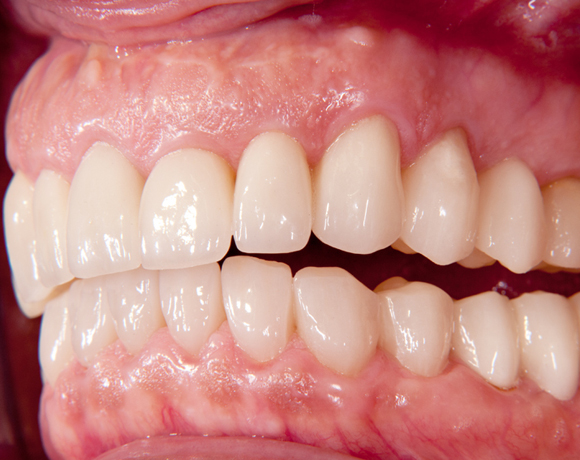

Der vorliegende Patientenfall zeigt eine komplette Neuversorgung der vorhandenen Metallkeramikkronen mit vollkeramischen Restaurationen. Zusätzlich wurde im Oberkiefer die Zahnreihe mit zwei Implantaten, für die fehlenden Molaren, ergänzt. Da keine ausreichende Knochenhöhe vorhanden war wurde ein interner Sinuslift geplant.